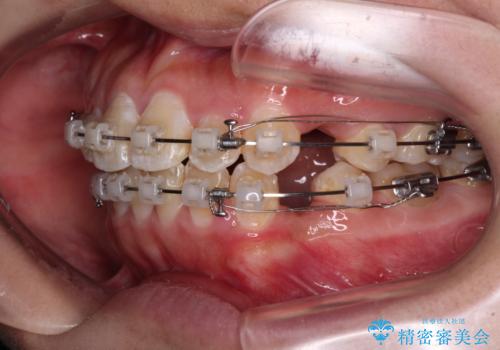

- クリアブラケット

- 前歯のクロスバイトと、口元が閉じにくいとのことで来院された患者様です。

口元の突出感を改善する必要があるため、上下左右の第1小臼歯4本を抜歯し、ワイヤー装置にて矯正治療を行うこととしました。

むし歯のリスクが高かったため、治療が長期化しないように心がけました。

当初の予定通り、2年強で無事に治療を終えることができました。